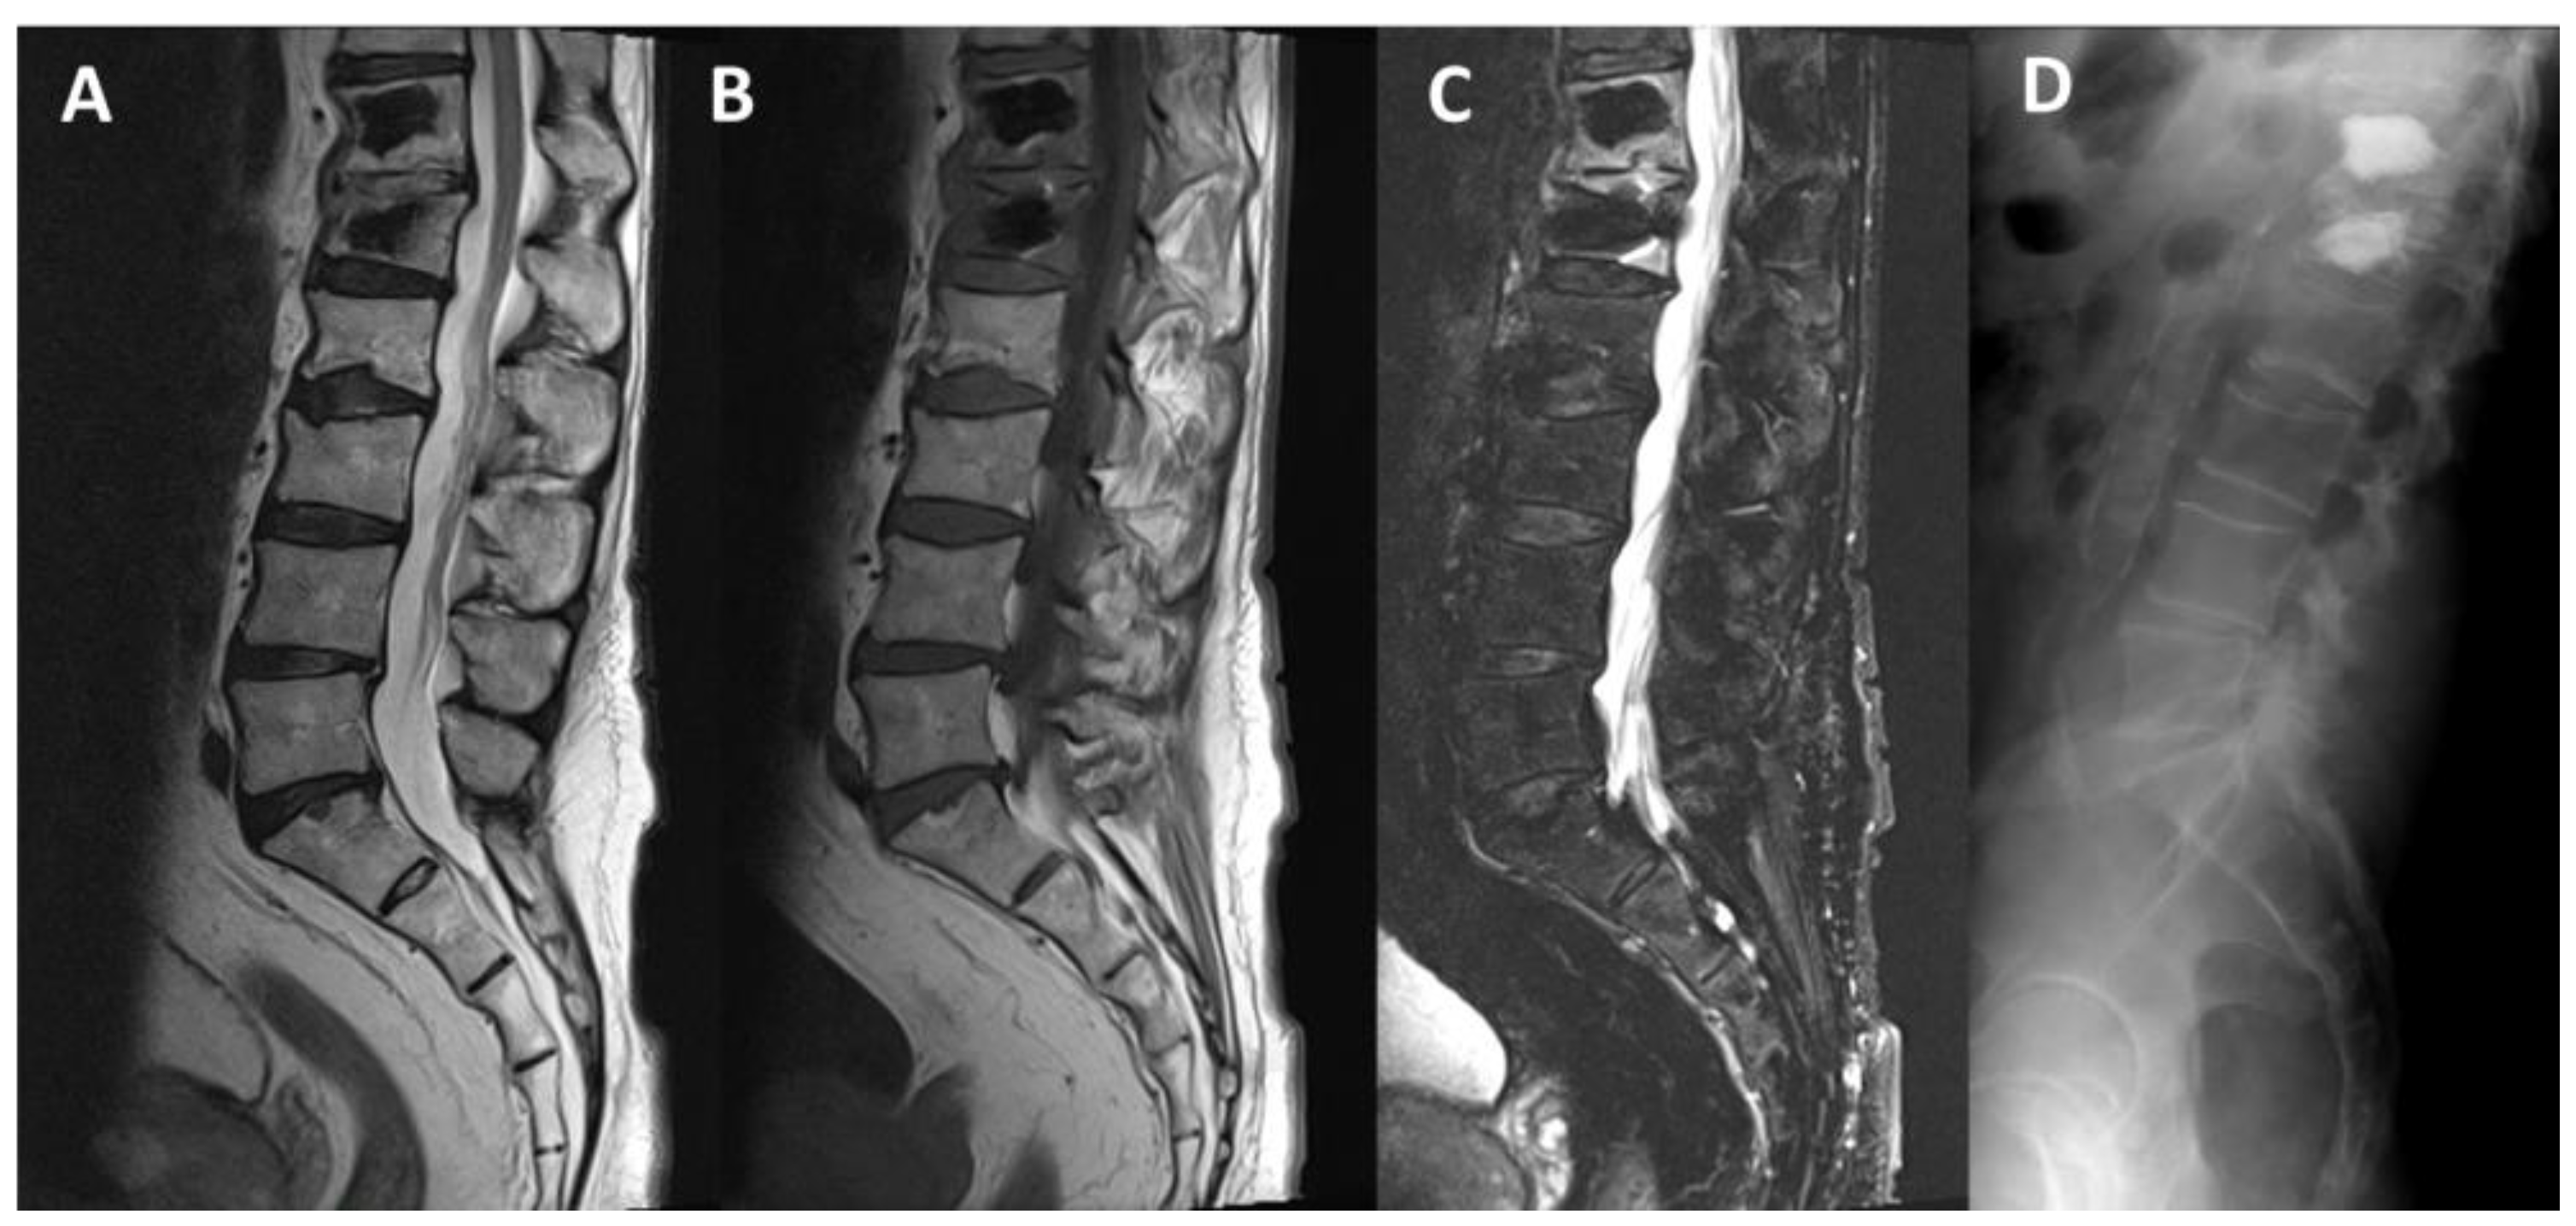

- Pusceddu, C.; Faiella, E.; Derudas, D.; Ballicu, N.; Melis, L.; Zedda, S.; Marsico, S. Re-expansion of vertebral compression fractures in patients with multiple myeloma with percutaneous vertebroplasty using spinejack implants: A preliminary and retrospective study. Front. Surg. 2023, 10, 1121981. [Google Scholar] [CrossRef]

- Pusceddu, C.; Marsico, S.; Derudas, D.; Ballicu, N.; Melis, L.; Zedda, S.; de Felice, C.; Calabrese, A.; De Francesco, D.; Venturini, M.; et al. Percutaneous Vertebral Reconstruction (PVR) Technique of Pathological Compression Fractures: An Innovative Combined Treatment of Microwave Ablation, Bilateral Expandable Titanium SpineJack Implants Followed by Vertebroplasty. J. Clin. Med. 2023, 12, 4178. [Google Scholar] [CrossRef]